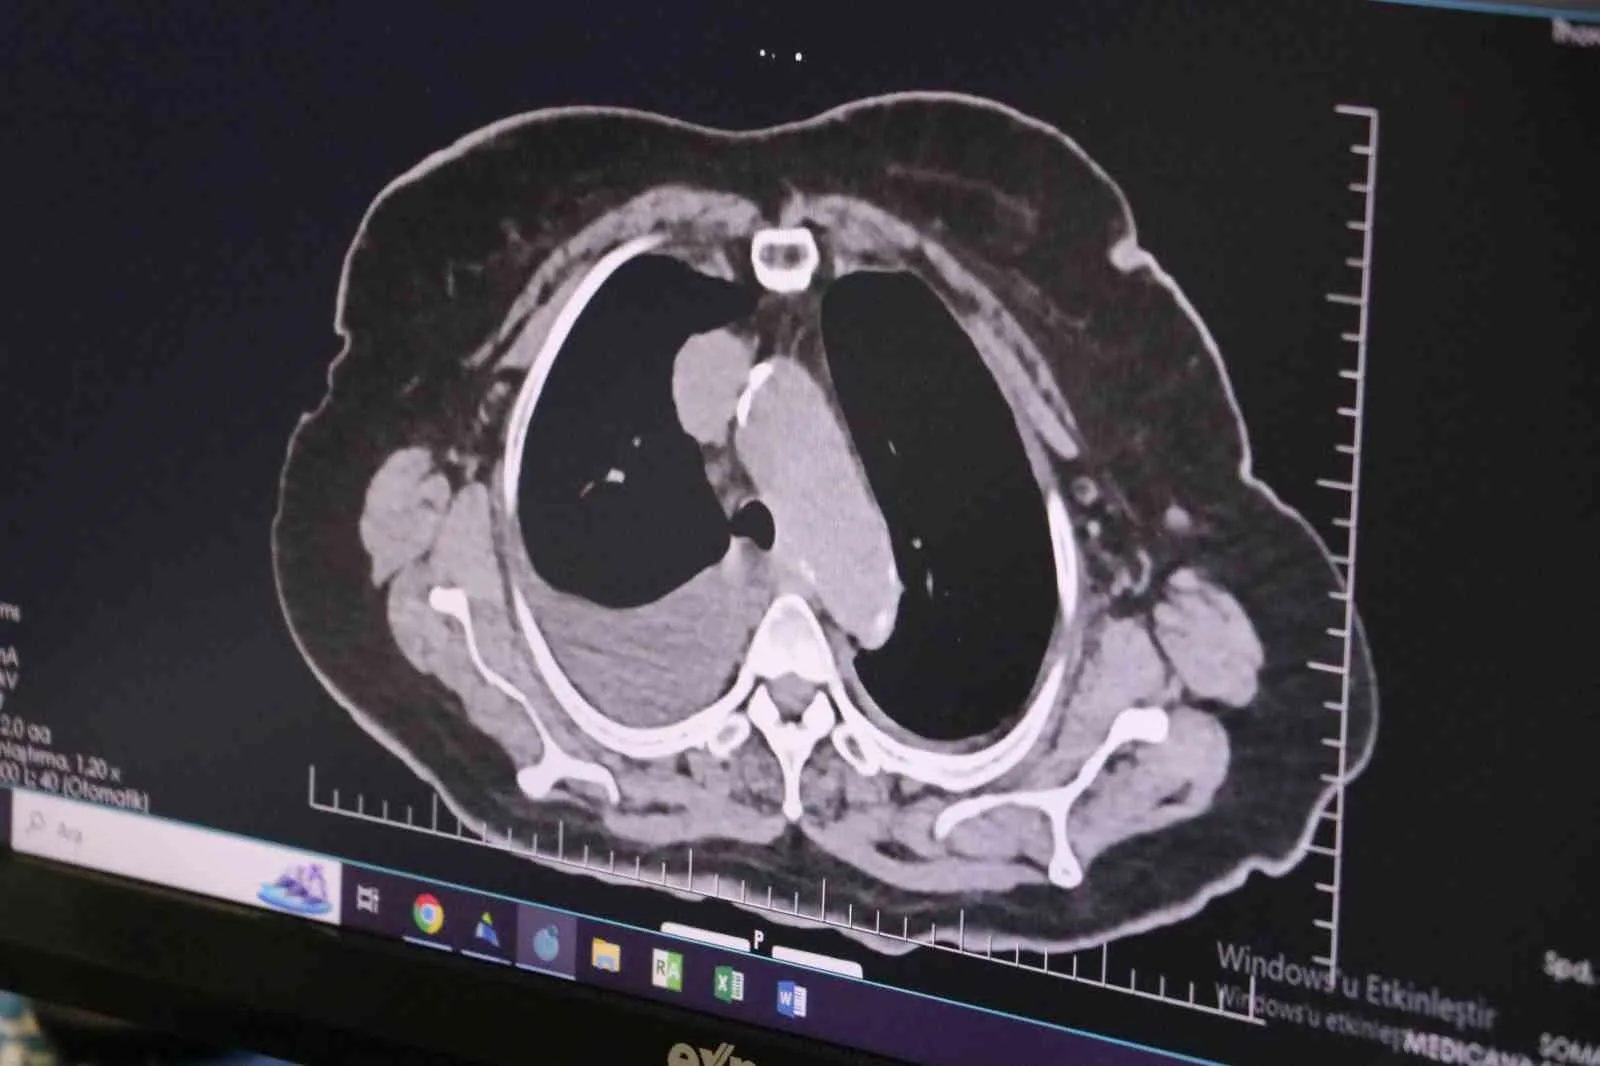

Kalp Sağlığı Haftası dolayısıyla konuşan Medicana Sivas Hastanesi Kardiyoloji Uzmanı Dr. İsmail Erdoğu, genç kuşakta kalp hastalıklarının artmaya başladığını ifade ederek, özellikle toplu yaşam alanlarında kalp masajı eğitiminin ve hayati müdahale cihazlarının bulundurulmasının önemine dikkat çekti.